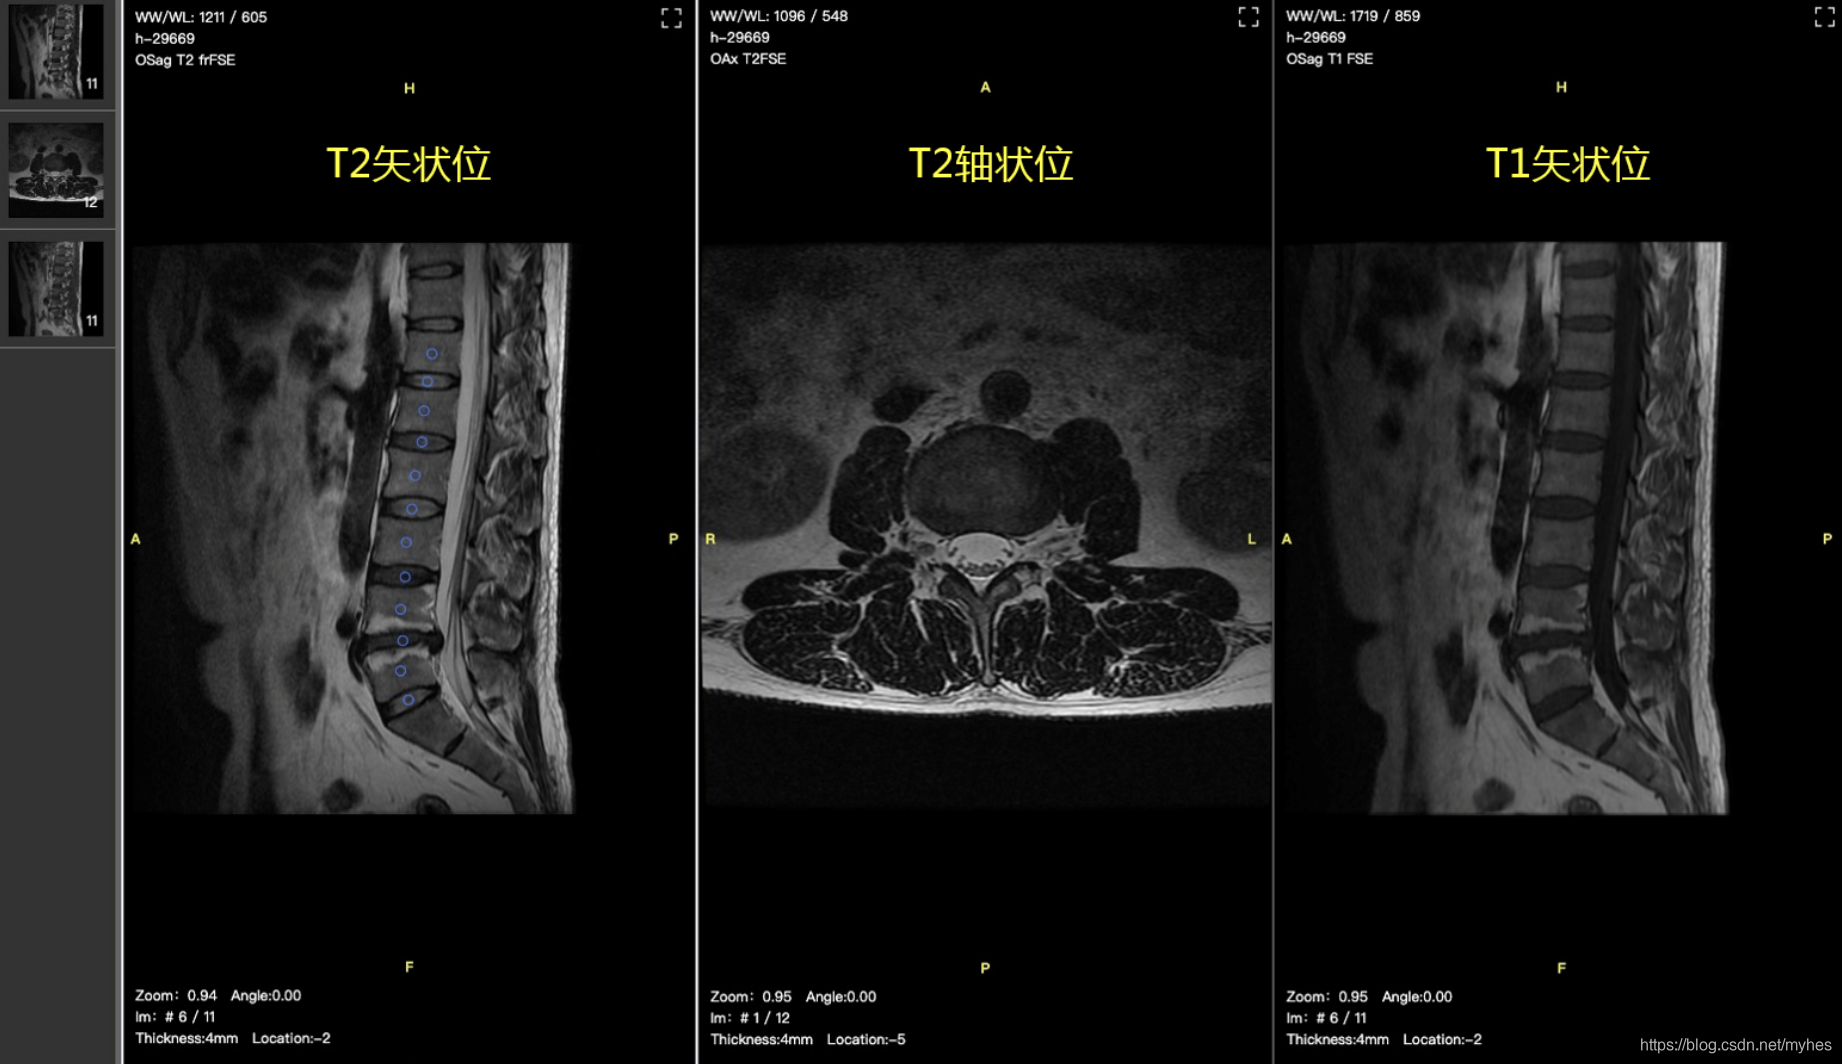

核磁共振成像(MRI)作为非侵入式检查手段,对软组织成像好,无辐射,对肌肉骨骼疾病的特异性和敏感度较高,适合对普通人群的常规检查,是预防脊柱退化性疾病的可靠检查手段。对肌肉和软组织的成像分辨率较高,便于诊断,主要用来观察神经、脊髓等椎管内软组织。

核磁共振影像包括T1和T2 矢状面影像,以及T2 轴状位影像(FSE/TSE),如下图:

核磁共振成像原理:原子核带有正电,许多元素的原子核,如1H、19FT和31P等进行自旋运动。通常情况下,原子核自旋轴的排列是无规律的,但将其置于外加磁场中时,核自旋空间取向从无序向有序过渡。自旋的核同时也以自旋轴和外加磁场的向量方向的夹角绕外加磁场向量旋进,这种旋进叫做拉莫尔旋进,就像旋转的陀螺在地球的重力下的转动。自旋系统的磁化矢量由零逐渐增长,当系统达到平衡时,磁化强度达到稳定值。如果此时核自旋系统受到外界作用,如一定频率的射频激发原子核即可引起共振效应。这样,自旋核还要在射频方向上旋进,这种叠加的旋进状态叫做章动。在射频脉冲停止后,自旋系统已激化的原子核,不能维持这种状态,将回复到磁场中原来的排列状态,同时释放出微弱的能量,成为射电信号,把这许多信号检出,并使之能进行空间分辨,就得到运动中原子核分布图像。原子核从激化的状态回复到平衡排列状态的过程叫弛豫过程。它所需的时间叫弛豫时间。弛豫时间有两种即T1和T2,T1为自旋-点阵或纵向驰豫时间,T2为自旋-自旋或横向弛豫时间。